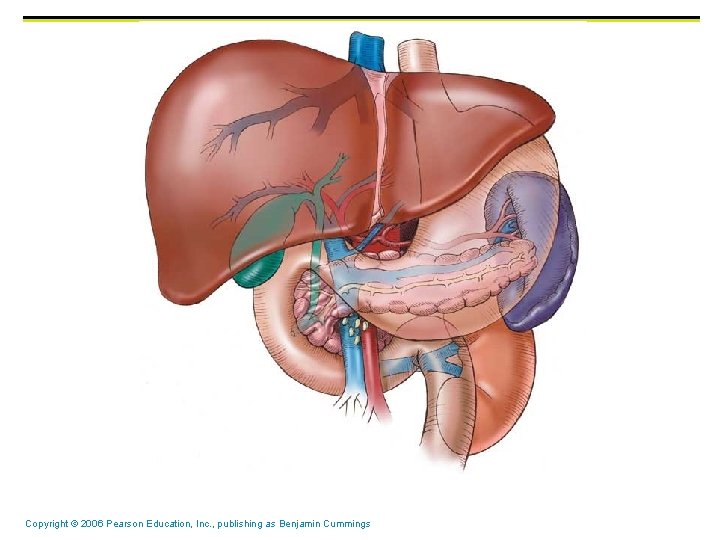

Liver (largest organ in body) & Gallbladder § Bile is produced in the liver and the Gallbladder stores bile Copyright © 2006 Pearson Education, Inc. , publishing as Benjamin Cummings

Gallbladder and Associated Ducts Copyright © 2006 Pearson Education, Inc. , publishing as Benjamin Cummings Figure 23. 20

Composition of Bile § § A yellow-green, alkaline solution containing bile salts, bile pigments, cholesterol, neutral fats, phospholipids, and electrolytes Bile salts are cholesterol derivatives that: § Emulsify fat § Facilitate fat and cholesterol absorption § Help solubilize cholesterol Copyright © 2006 Pearson Education, Inc. , publishing as Benjamin Cummings